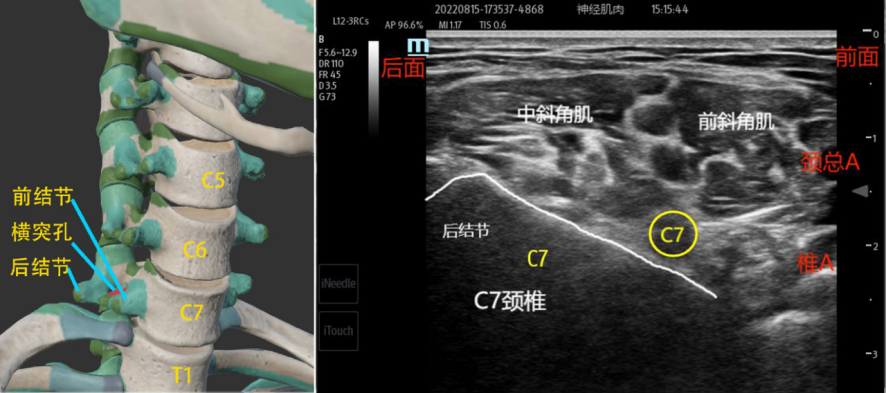

1、第7颈椎:其横突孔中无椎动脉走行(椎动脉一般从在C6前下方进入C6的横突孔)。且C7的前结节很小,后结节特别发达,这一解剖特点为超声扫查的一个重要定位的结构,即C7的横突在超声显像中,只呈一又粗又宽的强回声后方伴强声影的图像,常称为“斜坡征”或“椅背征”。

1、C7、C6、C5、C4颈椎定位法:C7颈椎:探头先放在锁骨上方,利用C7颈椎横突的前结节不明显的特点,上下滑动寻找到C7颈椎的横突,C7的后结节超声图像为一粗大“斜坡”或“椅背样”的骨骼声影。然后上下滑动,当往上滑动时,找C6颈椎,C6颈椎的前结节长,后结节短,呈手指笔画的“手枪”声像图形。再往上滑动探头找C5颈椎,C5颈椎的前结节和后结节一般长短相当,两者的夹角也较大,呈“大V字母”型的声像图像。探头继续往上平移,C4颈椎的前后结节较短,两者的夹角也较小,称为“小V”。